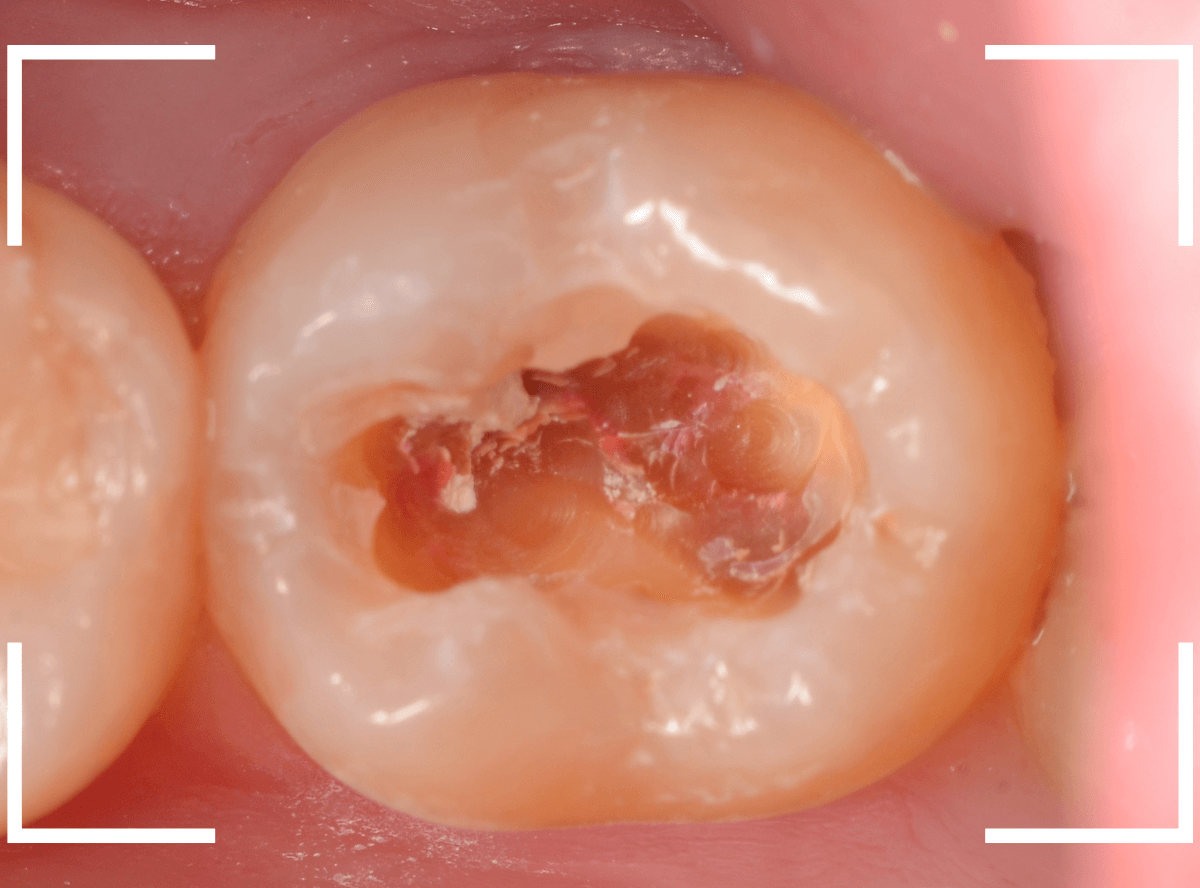

「つめものが外れて、噛むと痛い」という訴えで来院された患者さんさんです。

一見で、表面が虫歯になっているのと、レジンが劣化しているのがわかります。

レントゲン写真で確認します。

〇部が当該の歯です。

症状もあるので、虫歯が深そうですが、全体がもやっとして、どこからどこまで虫歯なのかはっきりわかりません。

まれに、こんな時もあります。

レジンを外し、虫歯の処置を進めます。

慎重に虫歯を除去し、一安心か、という寸前で(〇部、小さく出血しているところ)露髄してきました。

神経を除去しないとダメかもしれません。。。

神経を保護するお薬をつめて、経過観察します。

痛みが出ませんように。。。